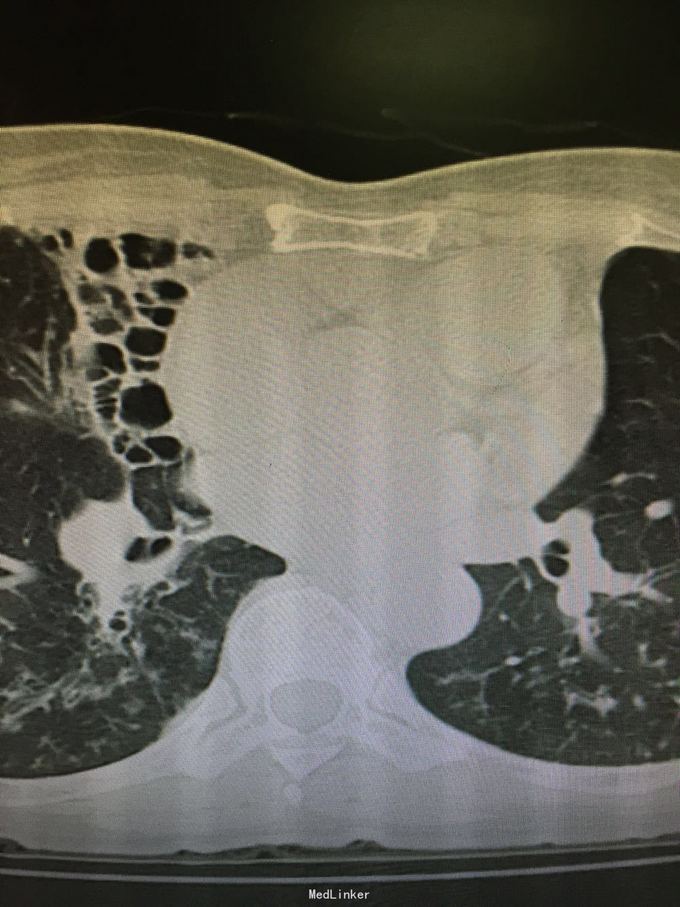

63岁女性,因“反复咳嗽、咳痰5年,加重1年”入院。

查体:双肺呼吸音粗,双上肺可闻及哮鸣音,双下肺可闻及干湿性罗音。外院胸片示两上中肺可见片装阴影,密度不均匀,边缘模糊,左中肺病灶中可见一椭圆形透光区,大小1.5*2.0cm;双肺纹理增粗、紊乱。考虑继发性肺结核(III上/上中。进展)我院胸片考虑支气管扩张。

诊断:支气管扩张并感染;肺结核?。入院后予甲磺酸左氧氟沙星200mlQd静滴治疗。

肺结核患者易并发支气管扩张。该患者影像学表现为碎饼干渣样,为较典型结核播散灶。支气管扩张表现也较典型。